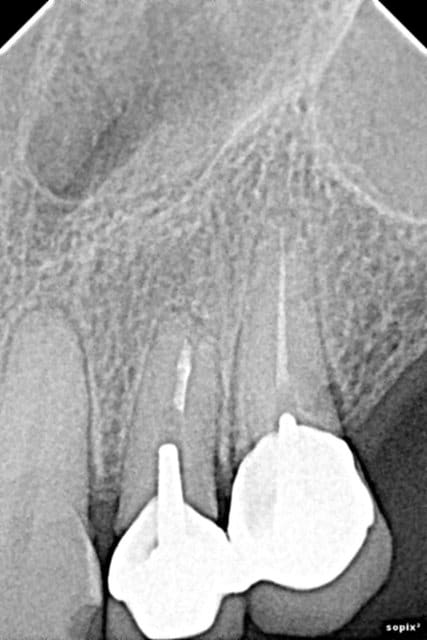

Moi j'aime pas l'apex de la 12... Préviens là quand même que ça peut ne pas durer si longtemps que ça pour cette dent. (idem 22)

Là est tout le problème... quel est l'avenir de ces dents antérieures ??

Est-ce que ça vaut le coup de les garder ? est-ce qu'on a 90% de chance que dans 5 ans la moitié soient à extraire...

3 sans hésiter (je ne vois pas grand chose sur la pano, trop petite sur mon écran)

Il faut, si on choisi la solution double sinus-lift, faire "vider" le sinus droit avant.

Au scanner, il est complètement obstrué certainement à cause du bout de pâte ou autre que l'on peut apercevoir sur la pano.